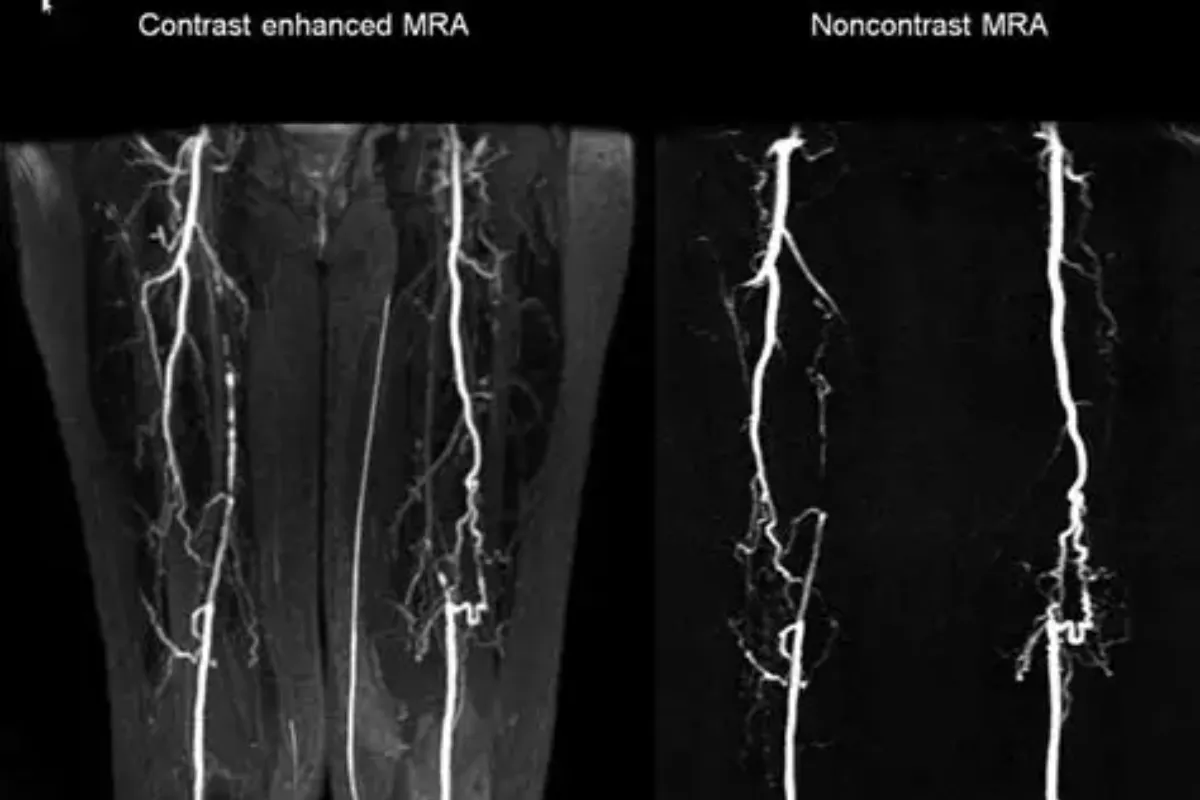

Interventional Radiology (IR) uses real-time imaging such as X-ray, ultrasound, CT, or MRI to guide tiny instruments through the body for treatment — without large surgical incisions.